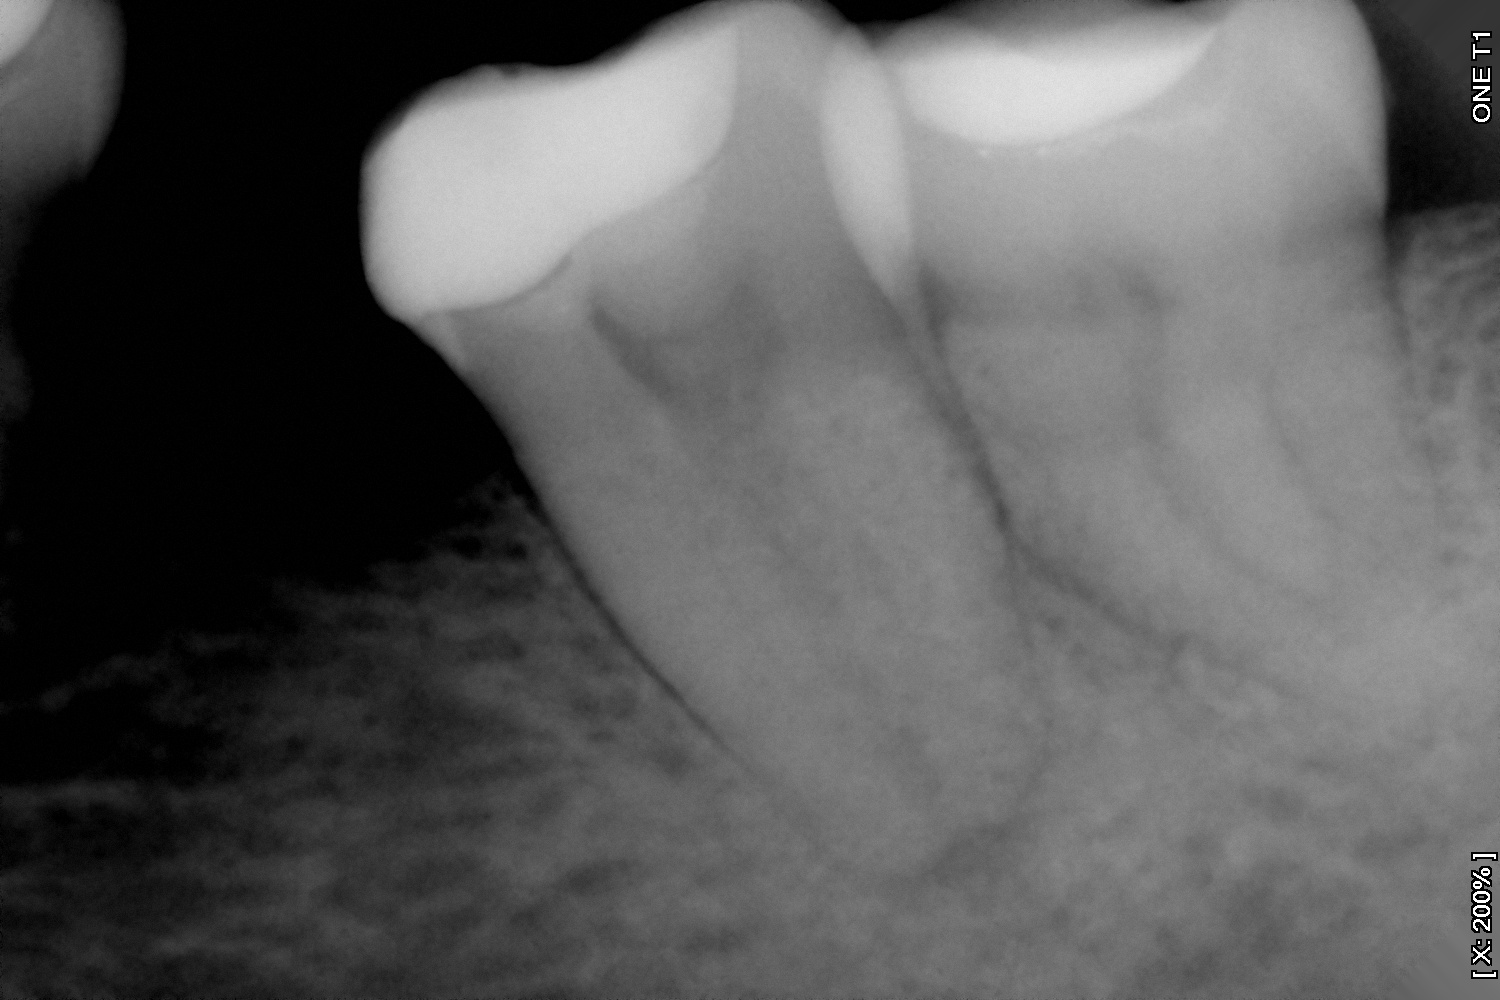

Es la especialidad que se encarga de retirar el nervio del diente cuando éste ha sido afectado por una caries, por un golpe o simplemente por requerimiento de un procedimiento de rehabilitación que esté causando sintomatología.

Y en DentPro realizamos tratamientos endodónticos con la más avanzada tecnología, utilizando sistemas rotatorios y radiografías digitales.